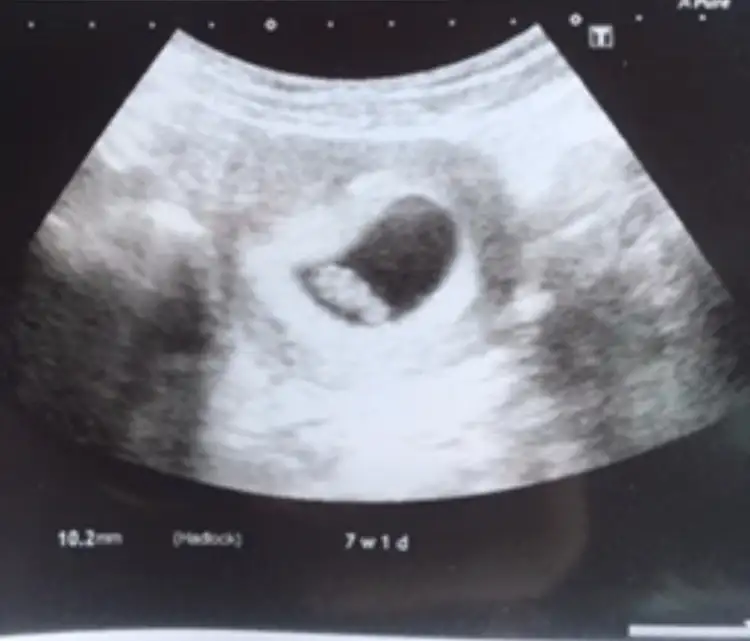

Öğrendiniz mi cinsiyetiniBu 6 haftalık olan

Benimkinde de bakar mısınız? 7 haftalıkİnşallah saglıkla gönlünüzdeki olur

Buna göre kız siz nub için 11 yada 12 hafta usg paylaşınSizce benimki nedir hanımlar? Karından usg ile bakıldıIkra meyra